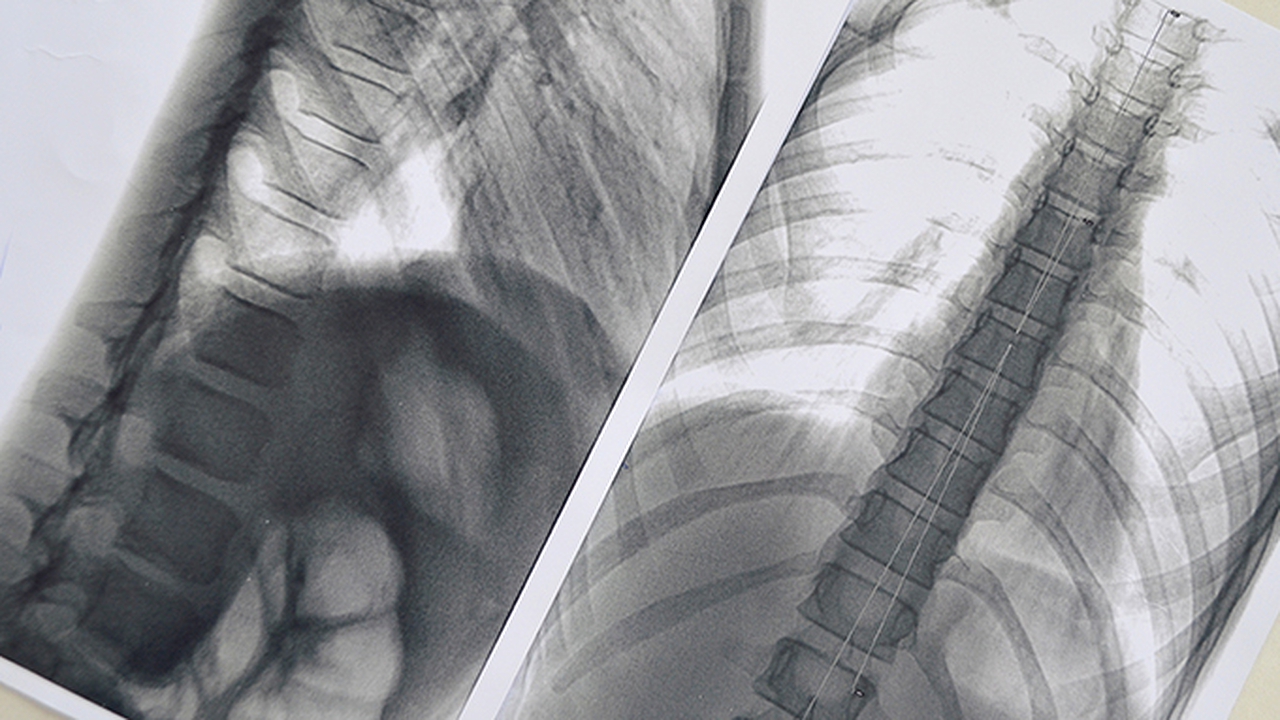

肺肿瘤的发病原因复杂,包括吸烟、空气污染、职业暴露、遗传因素等。早期诊断和规范治疗对提高患者生存率至关重要,因此选择专业医院尤为重要。

山东省肿瘤医院是全省的省级肿瘤专科医院,其胸部肿瘤科专注于肺肿瘤的诊疗与研究。科室开展包括手术、放疗、化疗、靶向治疗、免疫治疗在内的综合治疗,拥有TOMO刀、射波刀等放疗设备。医院参与制定多项诊疗规范,年收治肺肿瘤患者数量居全省。